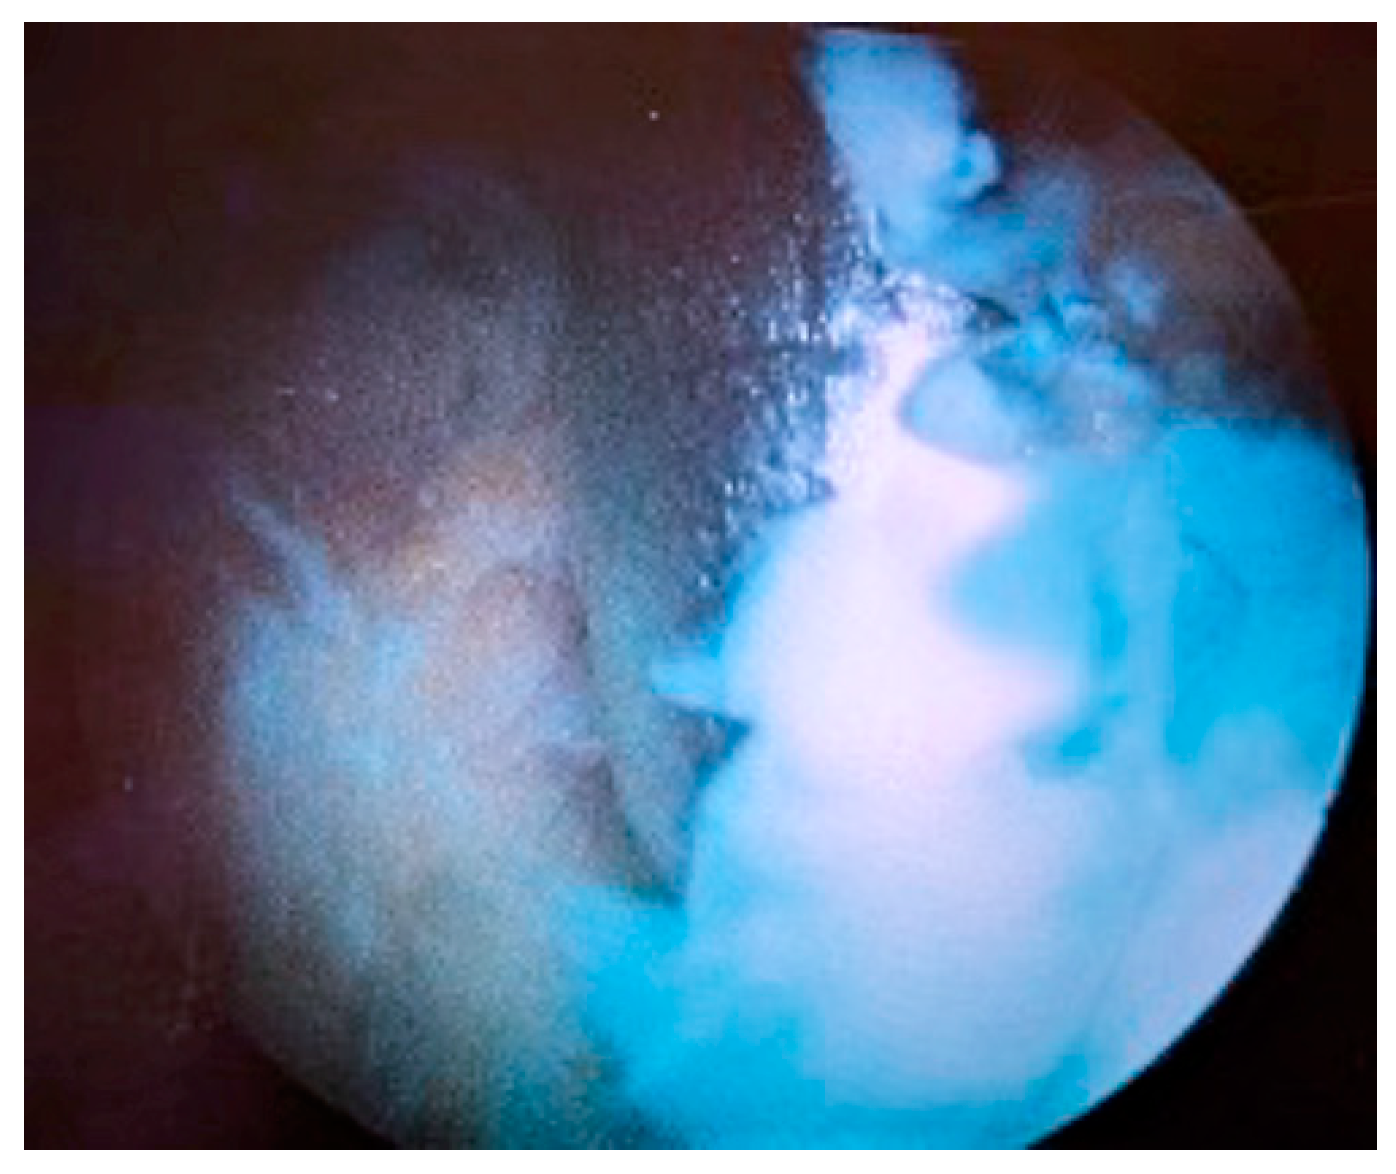

| Stage II | Severe inflammation, fibrinous deposition, pus, no radiological alterations |

| Stage III | Thickening of the synovial membrane, compartment formation (“sponge-like” arthroscopic view, especially in the suprapatellar pouch), no radiological alterations |

| Stage IV | Aggressive pannus with infiltration of the cartilage, possibly undermining the cartilage, radiological signs of subchondral osteolysis, possible osseous erosions and cysts |